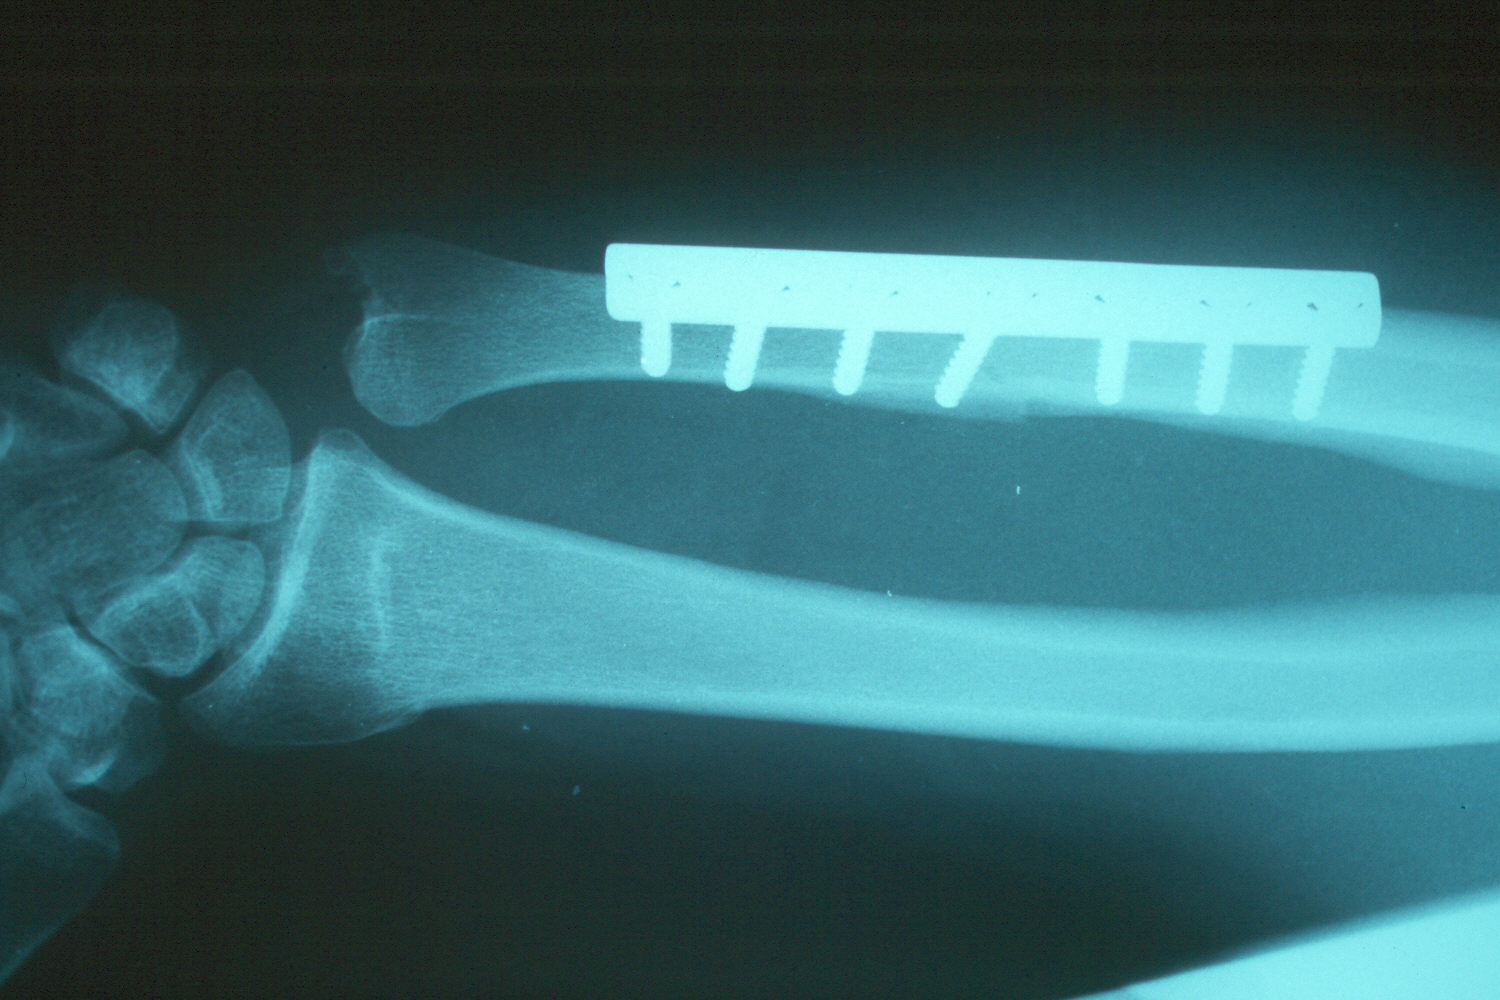

The osteotomy and plate position are planned using a seven hole plate with a compression screw positioned obliquely across the osteotomy cut.

Late result - healed.